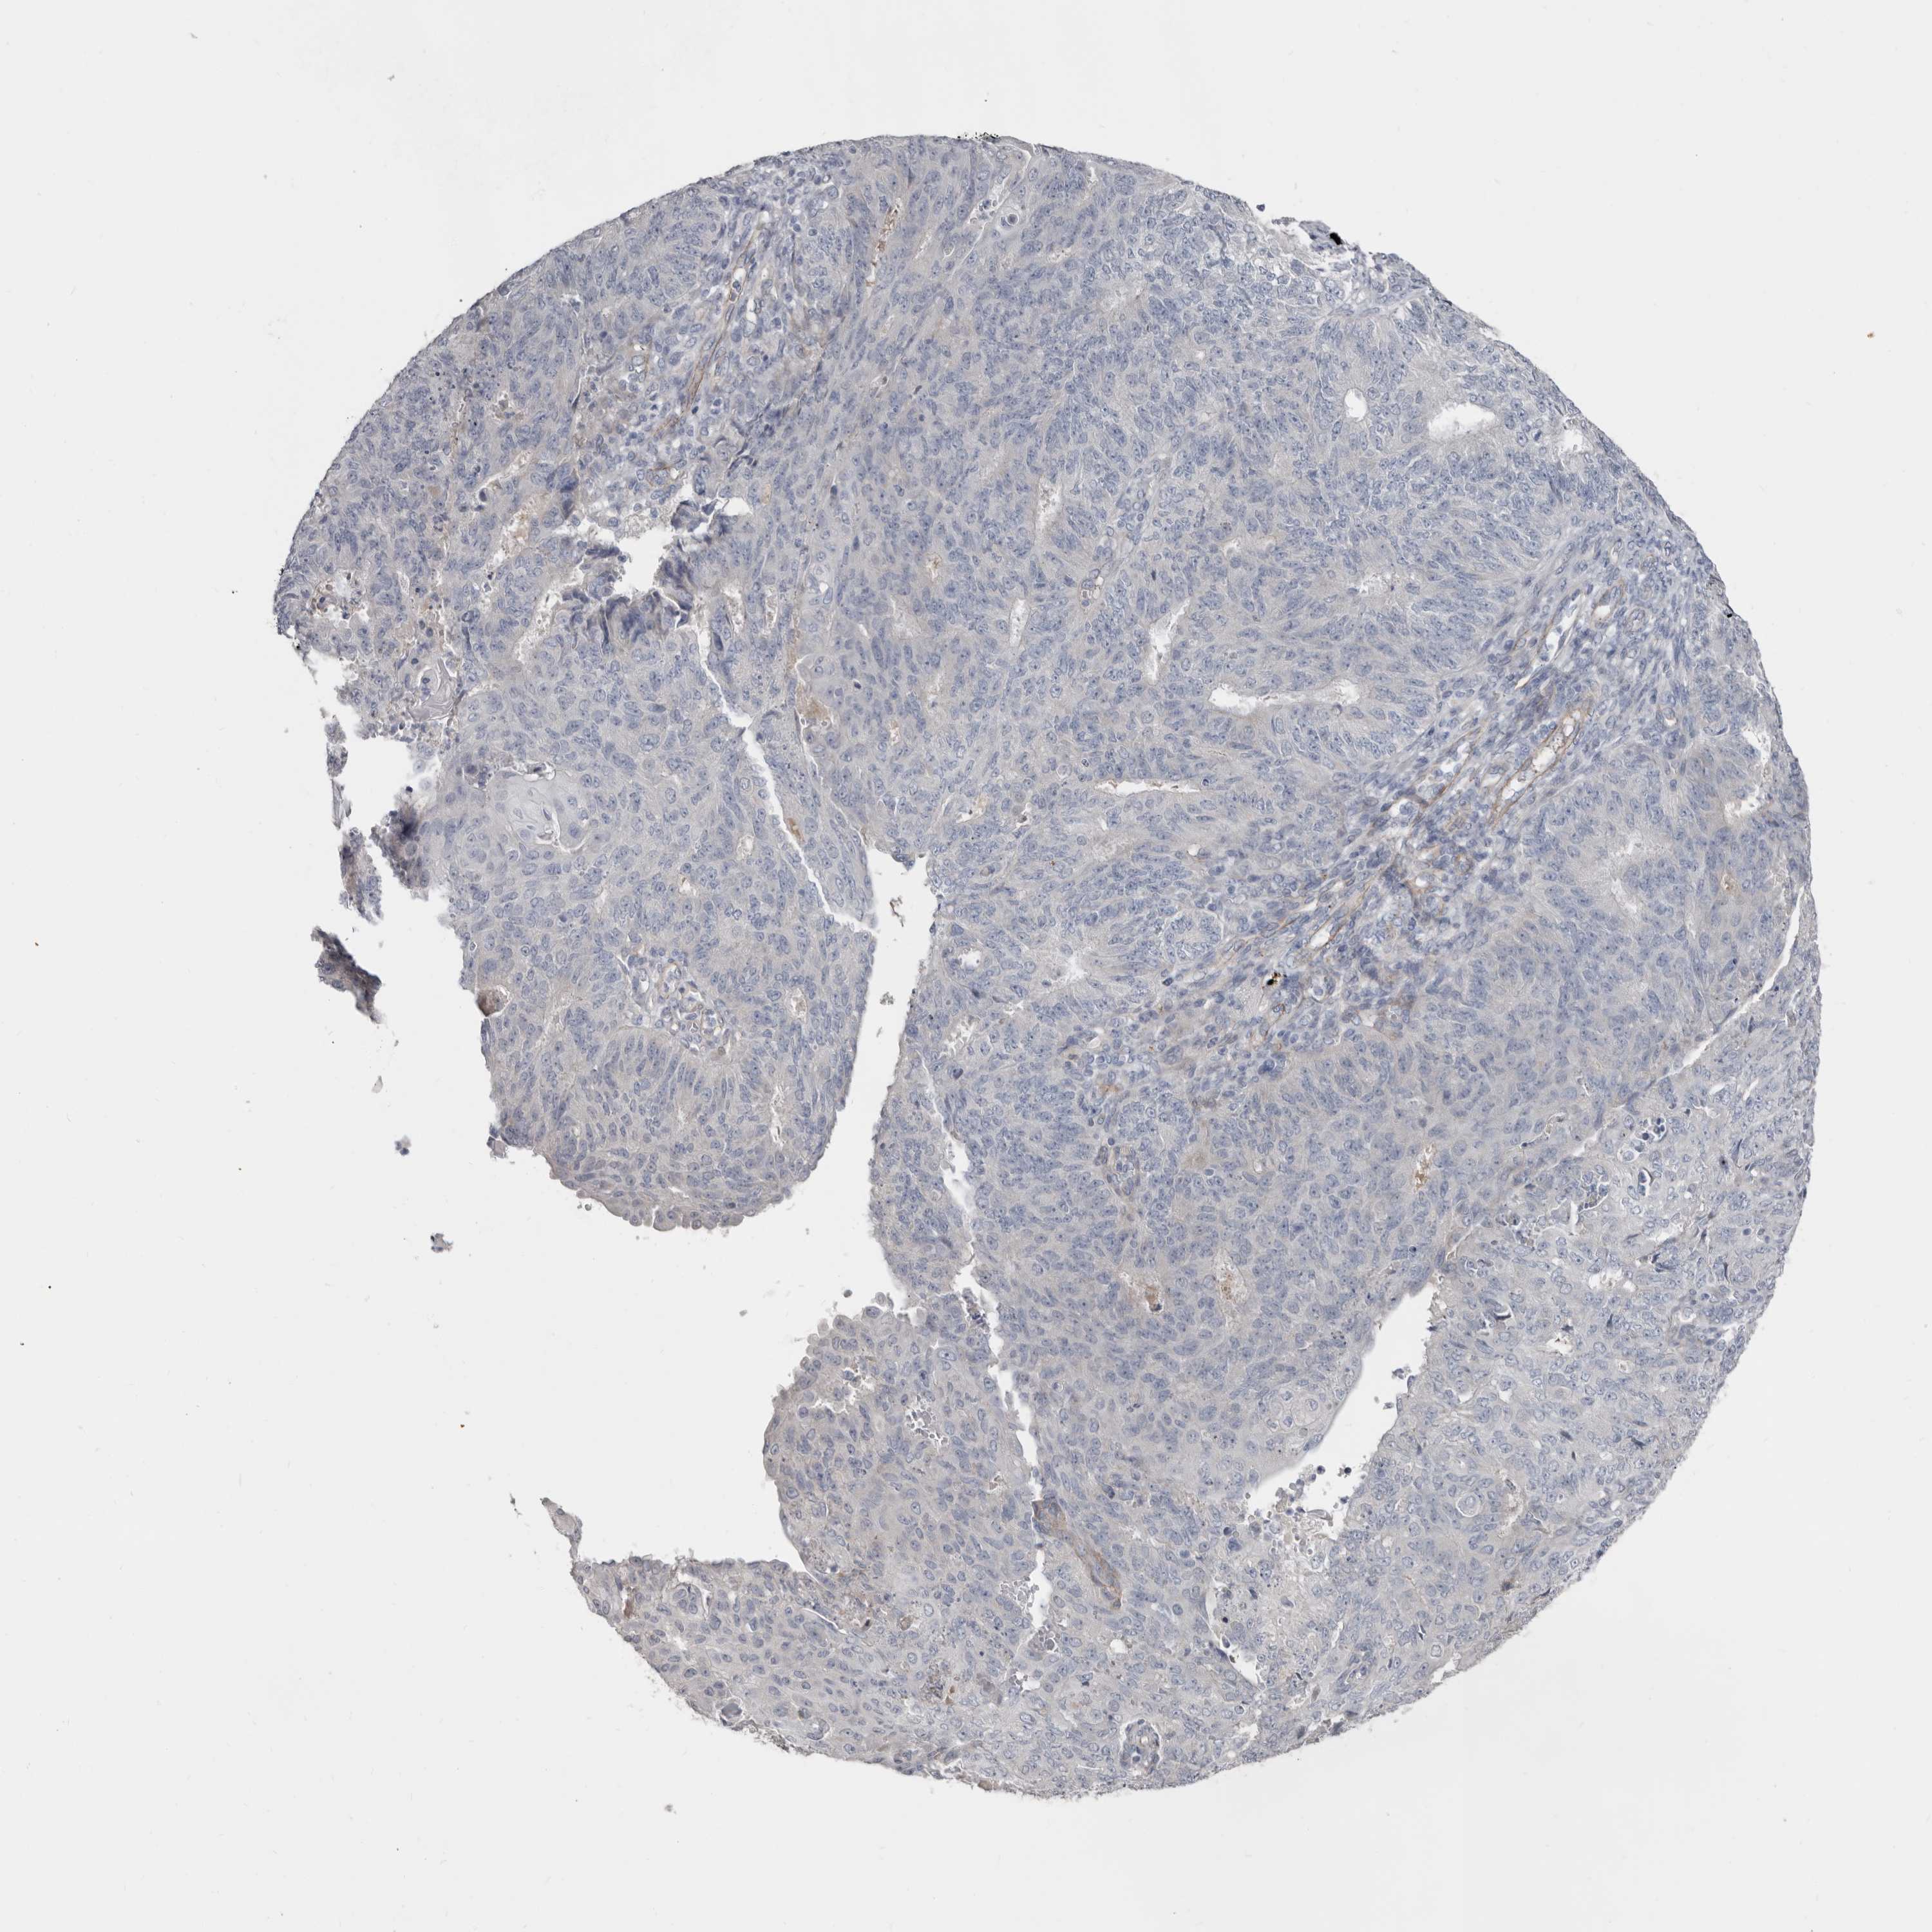

ENDOMETRIAL CANCER - Protein expressioni

A mouse-over function shows sample information and annotation data. Click on an image to view it in a full screen mode. Samples can be filtered based on level of antibody staining by selecting one or several of the following categories: high, medium, low and not detected. The assay and annotation is described here.

Note that samples used for immunohistochemistry by the Human Protein Atlas do not correspond to samples in the TCGA dataset.

Antibody stainingi

Antibody staining in the annotated cell types in the current human tissue is reported as not detected, low, medium, or high, based on conventional immunohistochemistry profiling in selected tissues. This score is based on the combination of the staining intensity and fraction of stained cells.

Each image is clickable and will lead to virtual microscopy that enables deeper exploration of all samples and also displays staining intensity scores, fraction scores and subcellular localization as well as patient and tissue information for each sample.

Antibody HPA025019

Antibody HPA029553

Staining

High

Medium

Low

Not detected

Intensity

Strong

Moderate

Weak

Negative

Quantity

>75%

75%-25%

<25%

None

Location

Nuclear

Cytoplasmic/membranous

Cytoplasmic/membranous,nuclear

Adenocarcinoma, NOS

Adenocarcinoma, metastatic, NOS